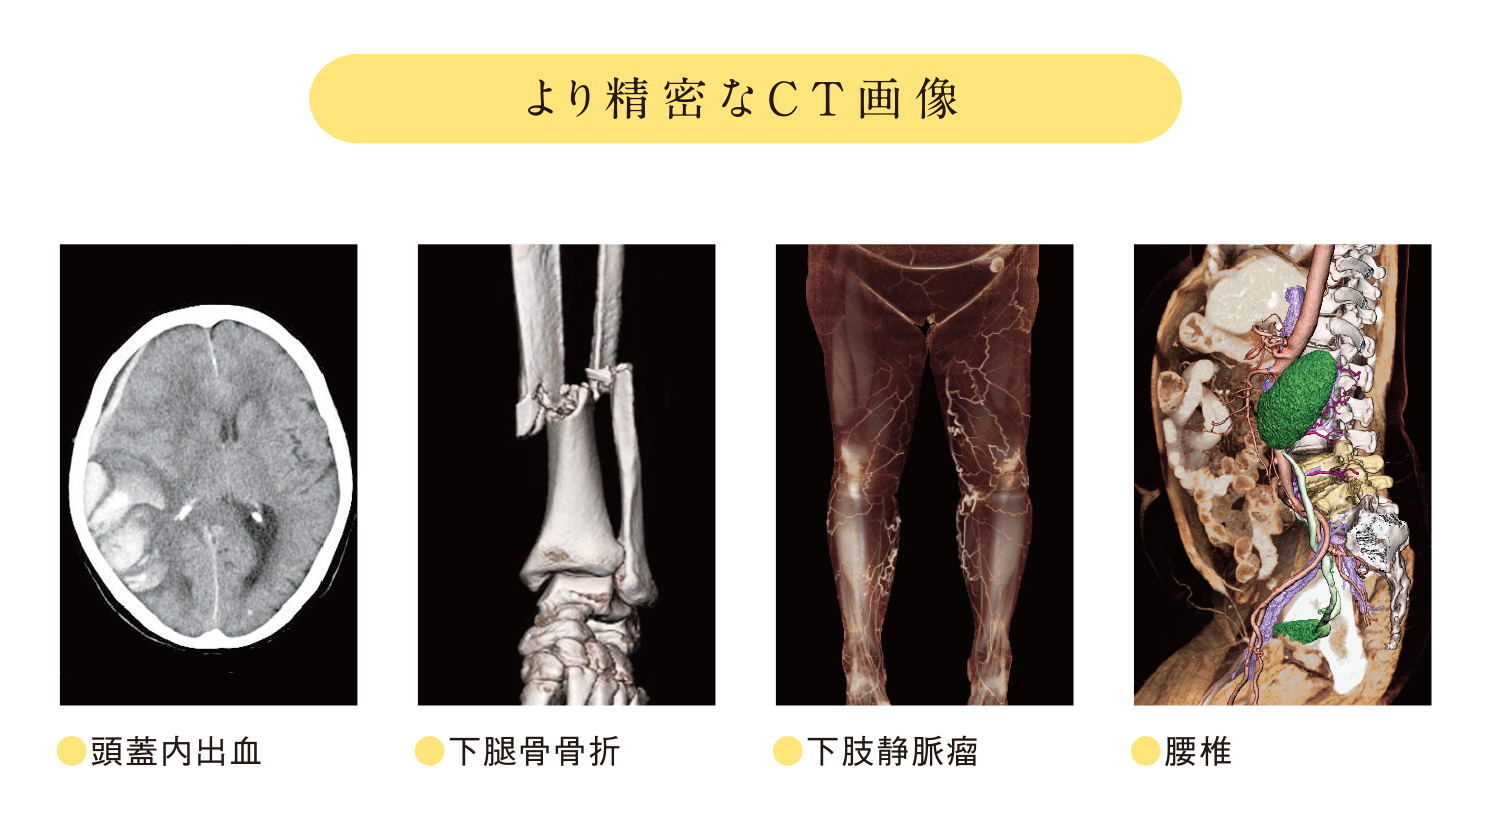

飛躍的に進化したCT検査

皆さん、CT検査の画像を見たことはありますか?CT画像はよく「体の輪切り画像」と表現されます。近年のCT装置の進歩は著しく、専門的な画像処理を施すことで「輪切り画像」だけでなく、様々な画像表示を行うことができるようになりました。上に示すのはほんの一例ですが、「3D画像」といって患者さまに疾患を説明する際や手術の前に綿密なシミュレーションを行う際に役立つものです。白黒のCT画像を用いて作成するのですが、色付けをすることで誰にでも疾患を理解しやすい画像となっていますこのように、現代の医療において患者様の病気を早期発見し、安心して安全に治療を受けていただく上でCT検査は必要不可欠となっています。

皆さん、CT検査の画像を見たことはありますか?CT画像はよく「体の輪切り画像」と表現されます。近年のCT装置の進歩は著しく、専門的な画像処理を施すことで「輪切り画像」だけでなく、様々な画像表示を行うことができるようになりました。上に示すのはほんの一例ですが、「3D画像」といって患者さまに疾患を説明する際や手術の前に綿密なシミュレーションを行う際に役立つものです。白黒のCT画像を用いて作成するのですが、色付けをすることで誰にでも疾患を理解しやすい画像となっていますこのように、現代の医療において患者様の病気を早期発見し、安心して安全に治療を受けていただく上でCT検査は必要不可欠となっています。

一方で、CT検査というと被ばく線量に関して不安を抱く方もいるかと思います。CT検査で受ける被ばく線量は微量であり、過度に心配する必要はありませんが、少しでも少ない被ばく線量で検査を受けたいと思うのが患者様の心理だと思います。そこで、私たちX線CT認定技師は、日額の線量を管理しつつ、患者様の疾患や治療法などに合わせて最適な検査を提供できるように、日々更新される最新技術の獲得やその有用性などを専門的に評価しています。私たちは複雑化した技術への対応を図りながらCT検査を実施し、様々な形でCT画像を提供することにより、患者様に寄り添うCT検査を目指しています。